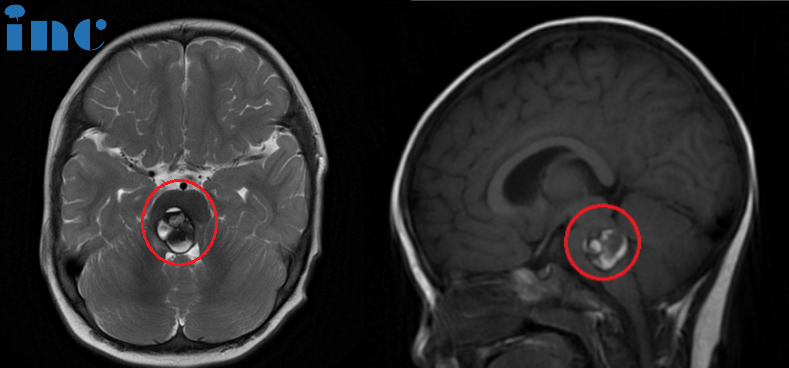

术前:脑桥占位。双眼斜视、畏光,面瘫,频发不自主扭头动作,走路稍有不稳。头颅MR (红色区域) 显示: 脑桥血肿,可见16 x 22 x 21mm肿块,第四脑室受压变窄。